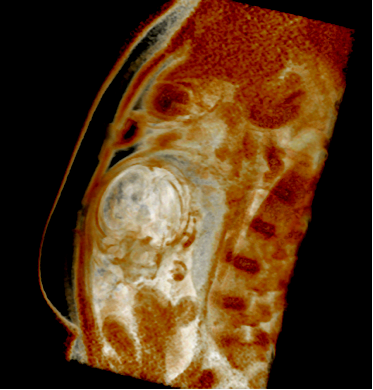

Fetal MRI